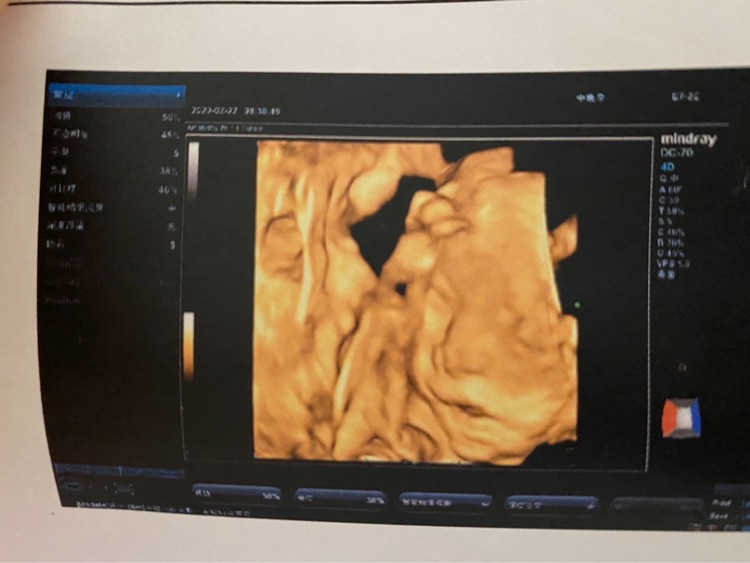

四维照片宝宝这样算兔唇吗